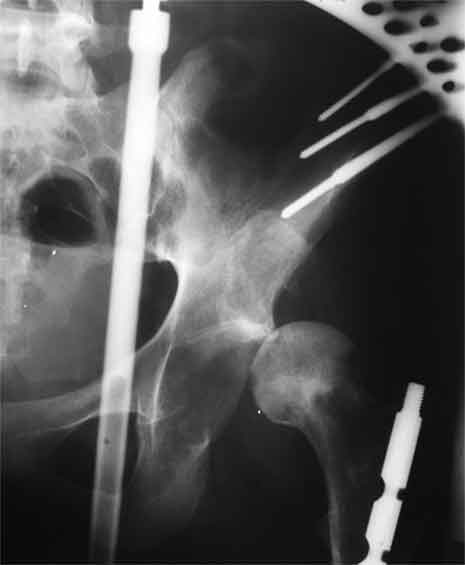

Насчет 8 см согласен с А.Н. Челноковым, это наверное ортопедическое за счет приводящей, сгибательной контрактуры и, возможно, колена. на ликвидацию укорочения у нас обычно уходит около 2-х нед. снимки в приложении, возможно не очень показательные, но других с ходу не нашел, завтра еще поищу.

Метод беcкровного низведения, предложенный Max&Co, мне кажется более логичным, чем поэтапность с удалением головки и с дальнейшим скелетним вытяжением.

Протезировать можно одномоментно, но тогда потеряется эффект от дистракции на мобильном аппарате. На дистрагированных мягких тканях по

Илизарову "закон напряжения растяжения" (tension stress) лучше делать реконструктивные операции, чем на контрагированных, твердых, как камень мышцах.

Другое преимущество - больной, самостоятельно передвигаясь, не будет обузой для обслуживающего персонала и в течение первого этапа может

находиться дома. После достижения дистракции отпадет необходимость предлагаемого двойного доступа с кровотечением!!, которые послеоперационно имеют большую вероятность осложнений, например, вывих протеза из-за ослабления сустава со всех сторон.